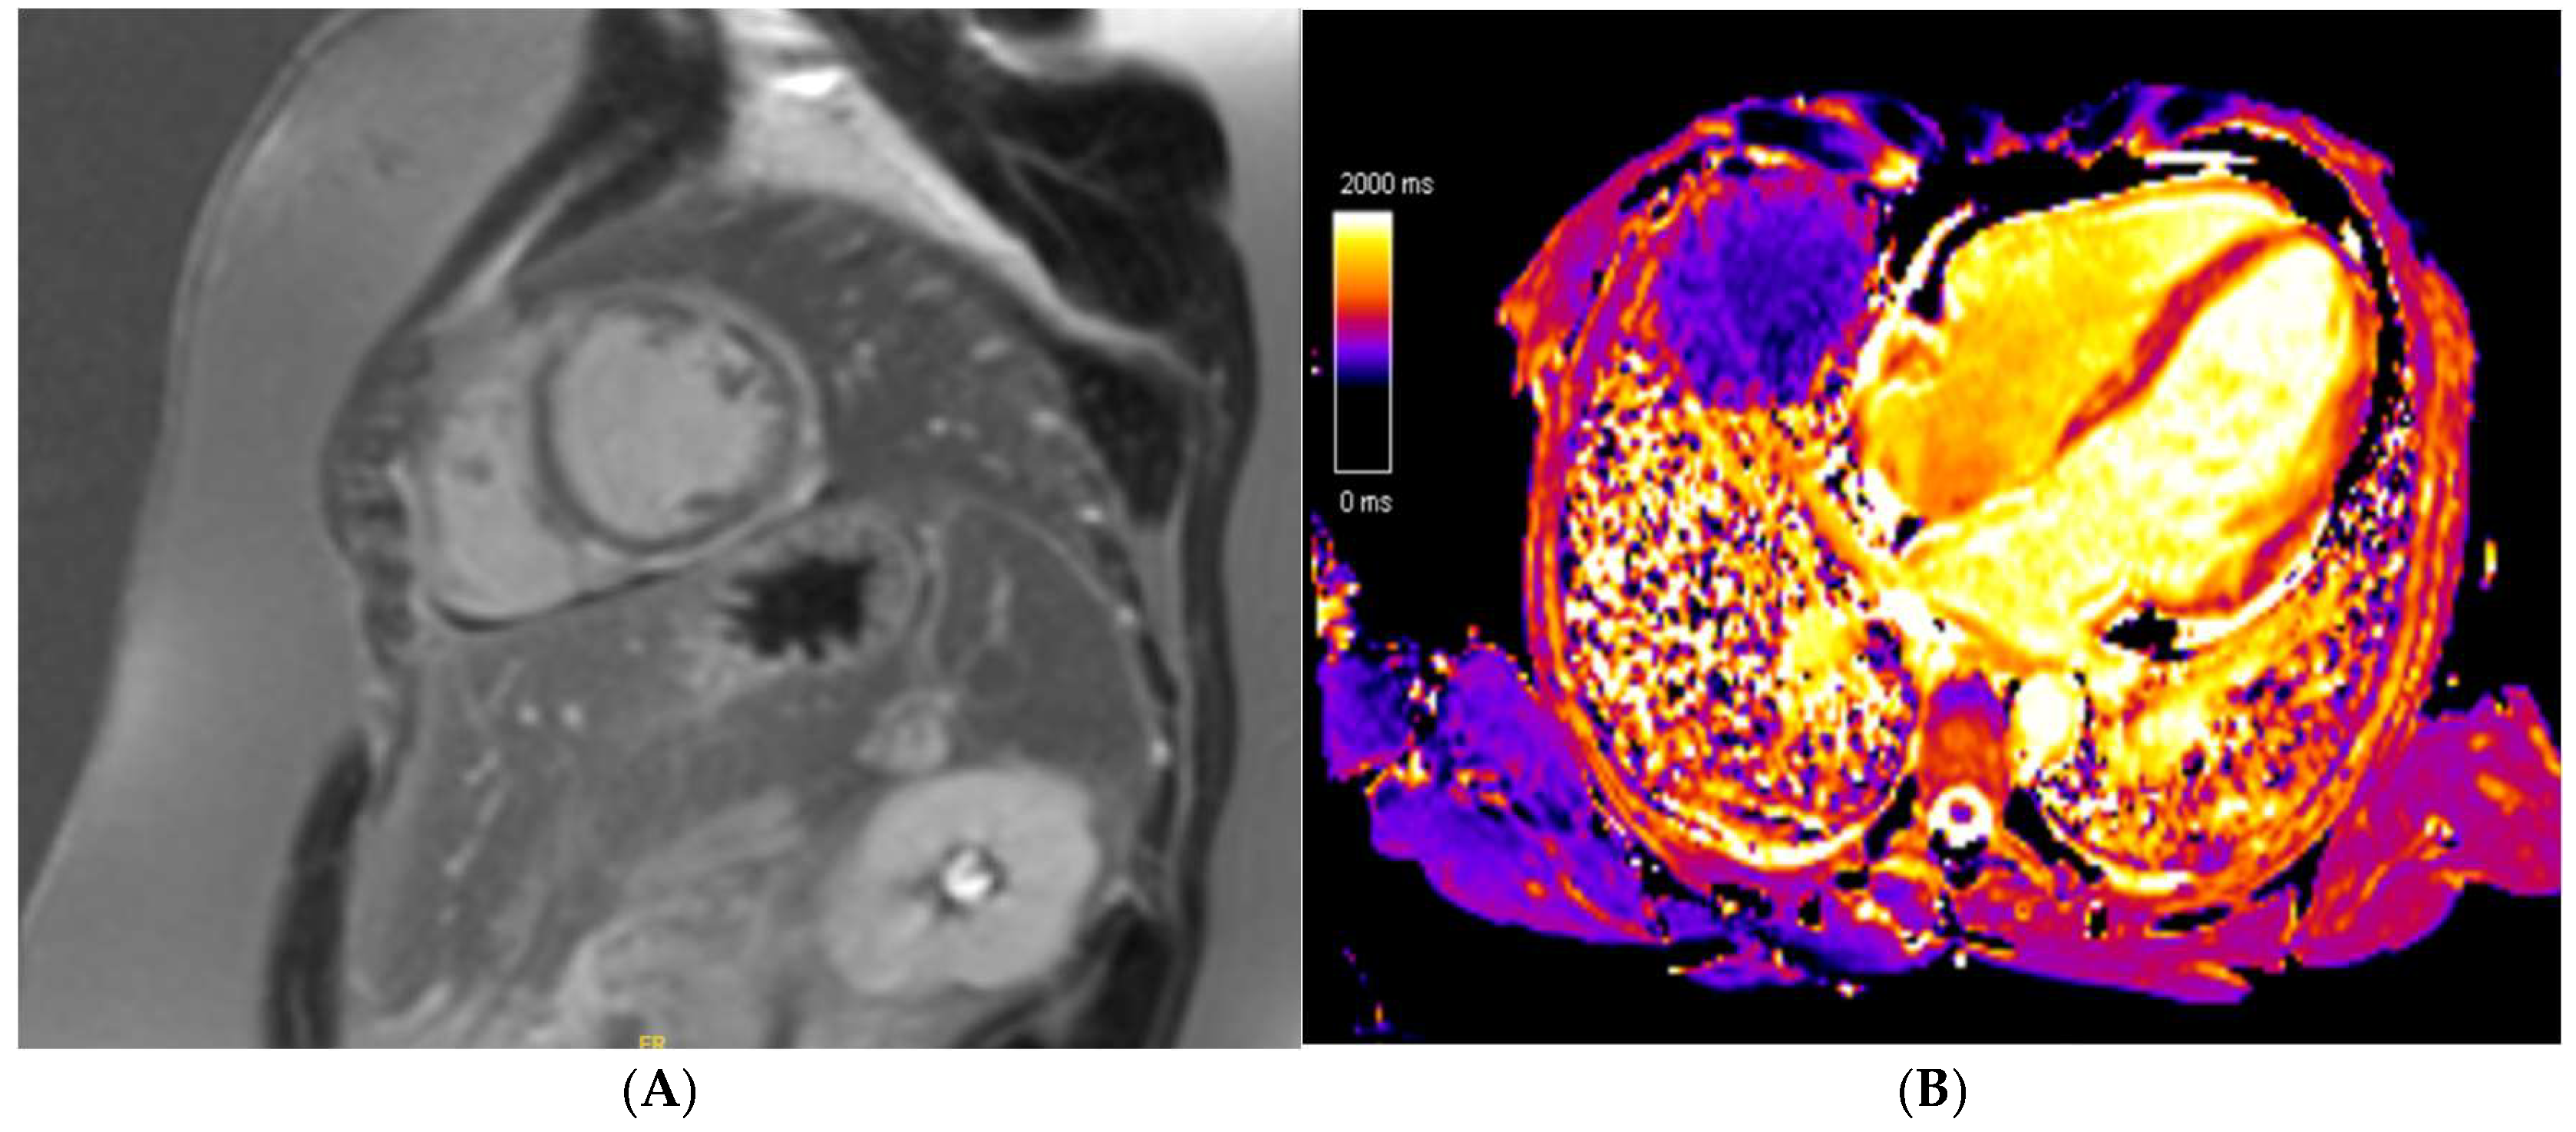

3.3. Technical Challenges—Practical Tips

4. Athlete’s Heart

7. Hypertrophic Cardiomyopathy